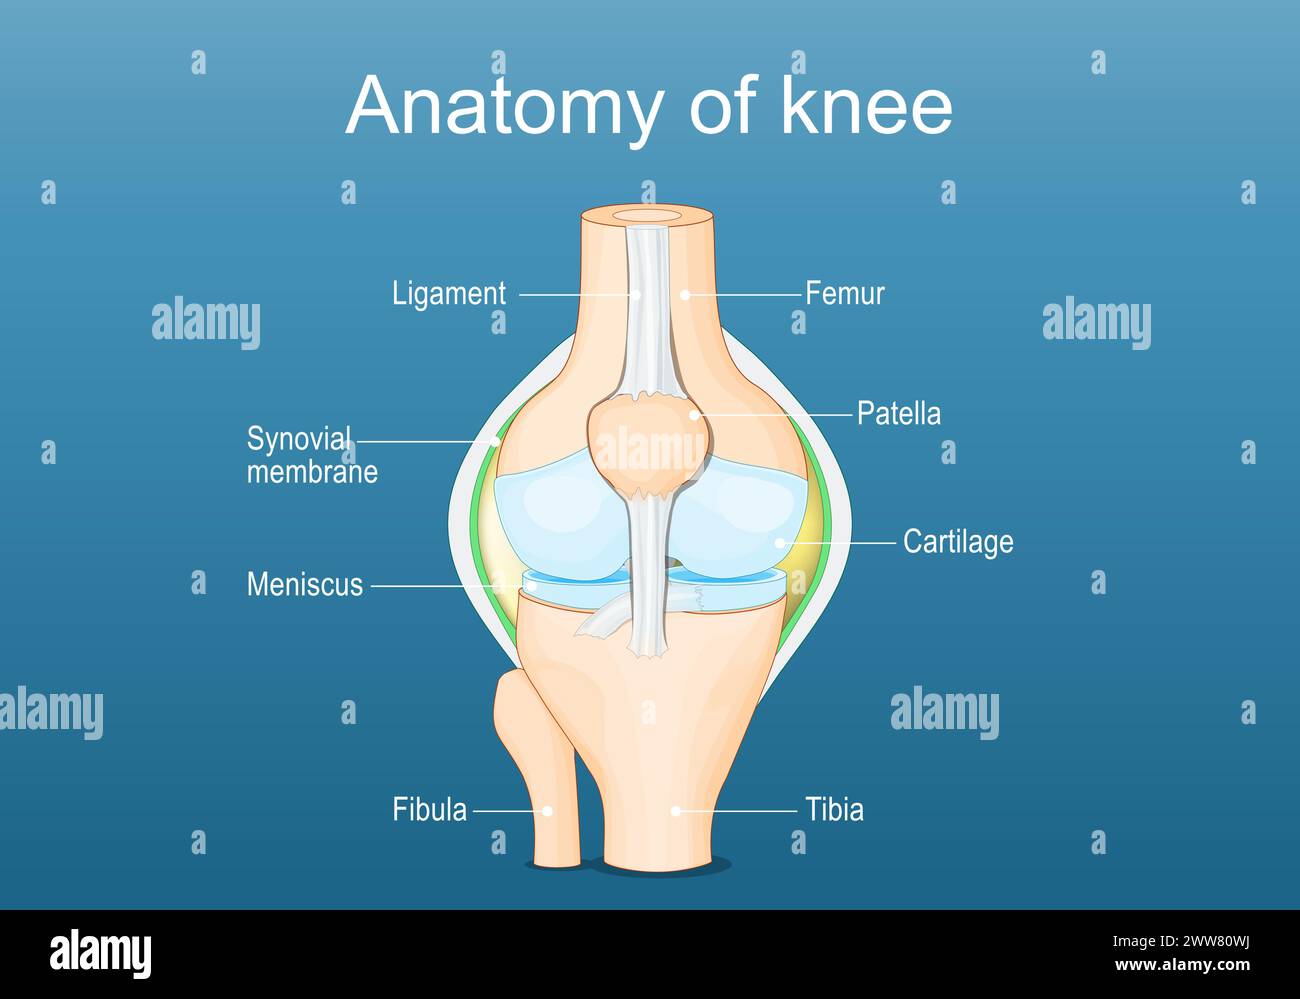

Knee joint anatomy. Labeled of all bones. Isometric Flat vector illustration Stock Vectorhttps://www.alamy.com/image-license-details/?v=1https://www.alamy.com/knee-joint-anatomy-labeled-of-all-bones-isometric-flat-vector-illustration-image600695246.html

Knee joint anatomy. Labeled of all bones. Isometric Flat vector illustration Stock Vectorhttps://www.alamy.com/image-license-details/?v=1https://www.alamy.com/knee-joint-anatomy-labeled-of-all-bones-isometric-flat-vector-illustration-image600695246.htmlRF2WW80WJ–Knee joint anatomy. Labeled of all bones. Isometric Flat vector illustration